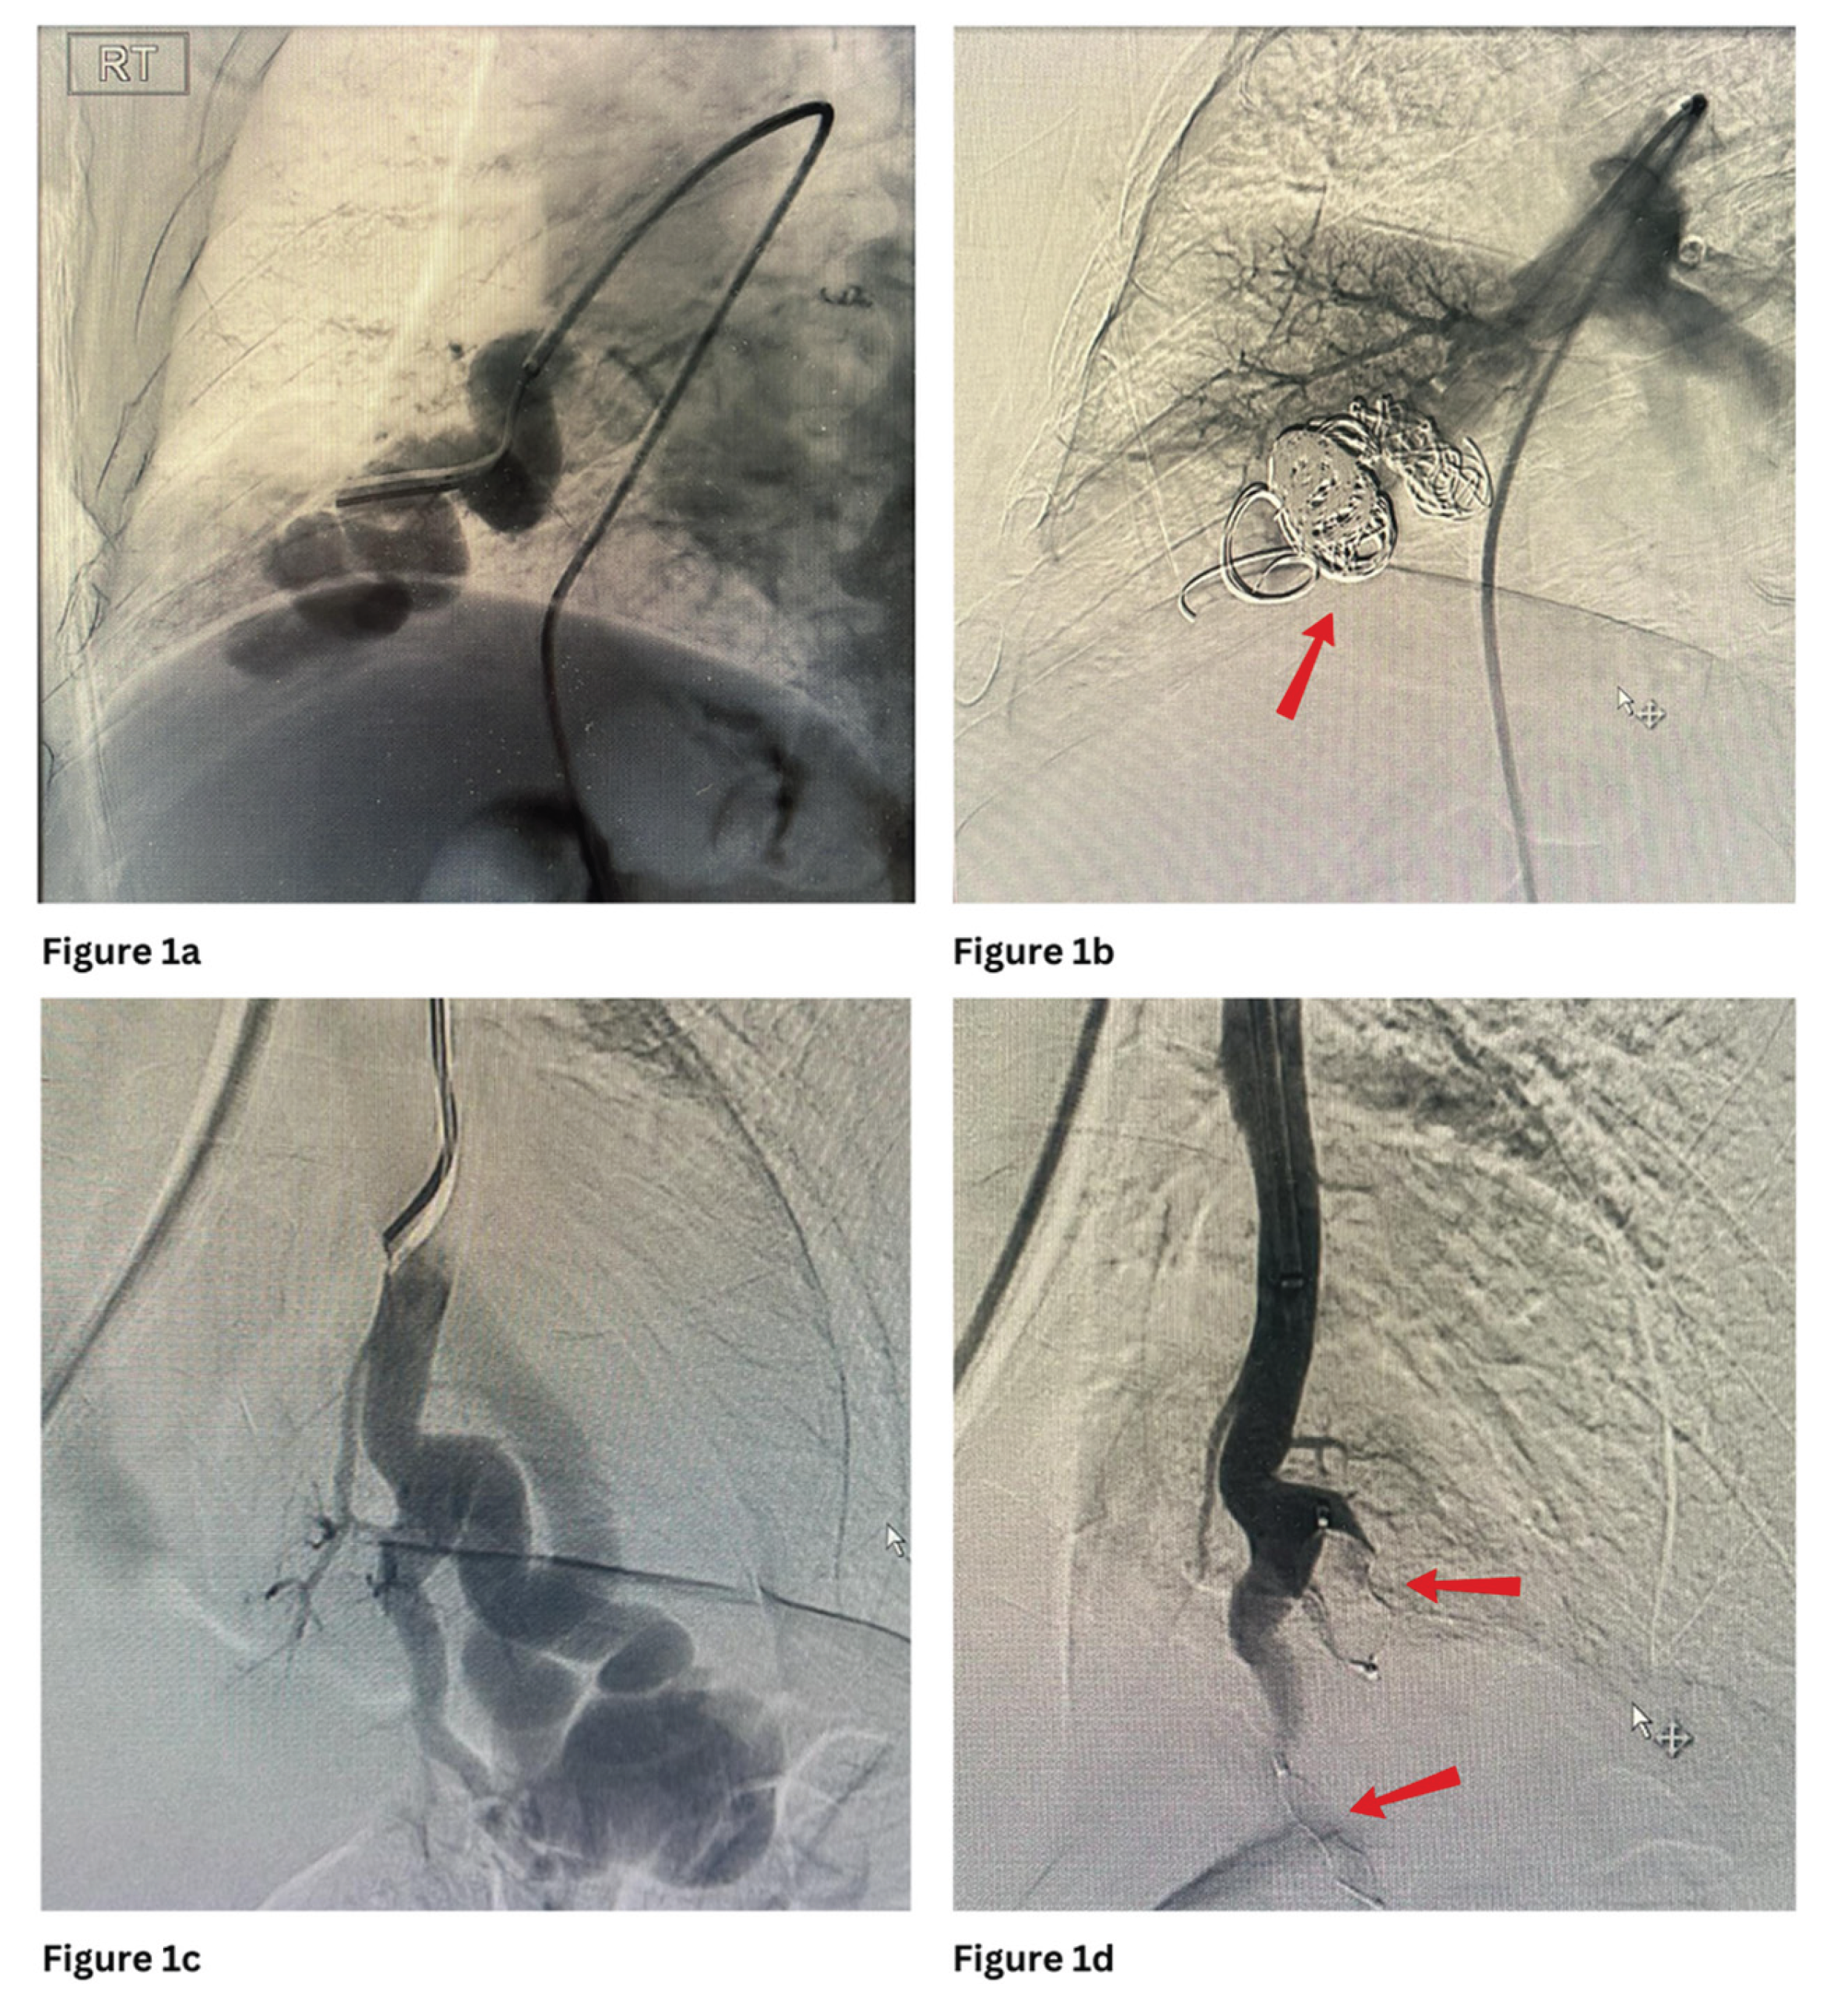

Figure 2a and 2b show embolisation of PAVM with MVP with occlusion of the feeding artery and further filling of the venous sac.

Figure 2. a and b show pre and post embolization of the PAVM with an MVP plug at the left lingular lobe. c and d show pre and post embolization of the complex PAVM with 1 AVP plug and a coil at the right lower lobe.